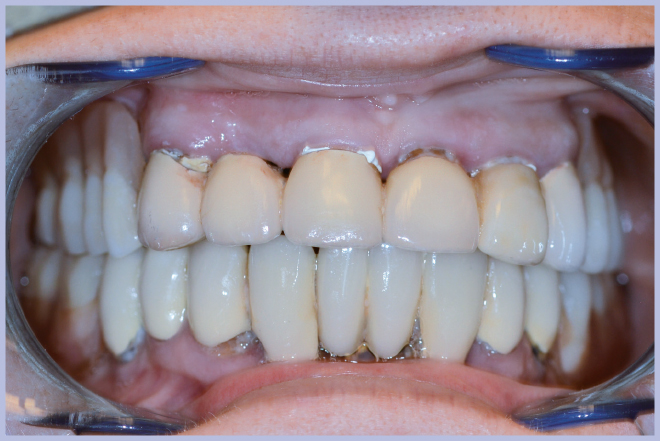

La semplicità della componentistica Leone ha permesso di completare l’intero trattamento in circa 6 ore e mezzo, consegnando alla paziente la protesi ultimata nella stessa giornata della chirurgia (Figg. 11-13).

- Fig. 11 – Consegna della protesi rifinita

- Fig. 12 – Sorriso della paziente al termine dell’intervento